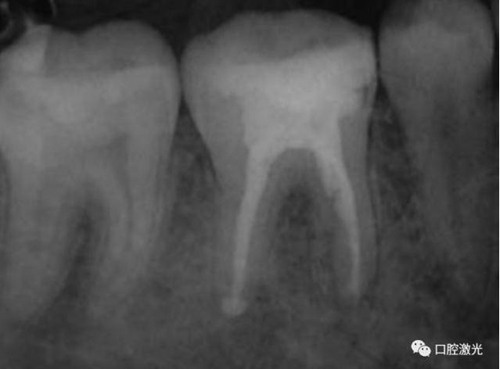

46治療前X光片

半導(dǎo)體激光治療中

6個(gè)月后治療效果